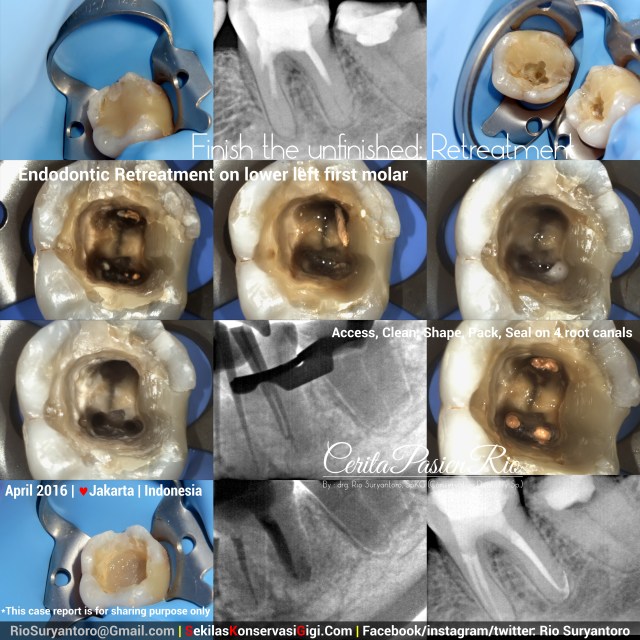

Retreatment: Finish the Unfinished

A patient with regular spontaneous pain came for having a dental treatment. This tooth had been treated (endodontic treatment and final coronal composite resin restoration) but the symptomps haven’t relieve at all.. in an xray examination, we can see a short obturation.

After taking a proper consent, I started to drill the coronal filling, access preparation, removal of previously placed gutta percha obturation, cleaning and shaping of all 4 canals with ProtaperNext (Dentsply) + Sodium Hypochlorite 5,24%. And obturate the root canals prior to coronal seal placement with low_shrinkage_stress flowable composite resim filtek_bulkfill (3M).

Xray evaluation using VistaRay (Durr) at 60kV, 3mA, and 0,03 seconds.